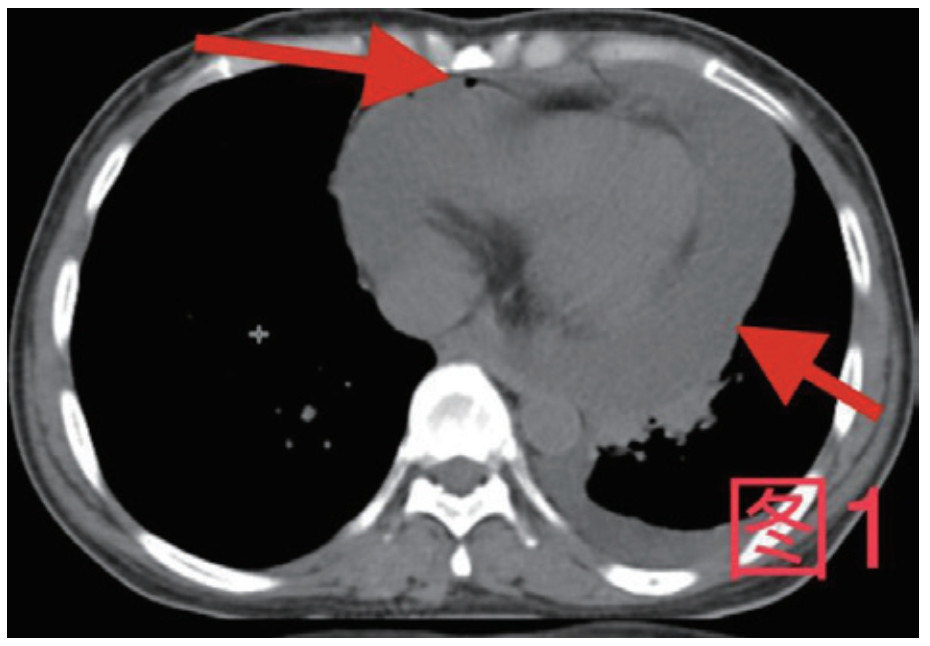

患者,女,41岁,2020年10月26日因“腹痛3 d”入急诊,否认近期有吞服异物、鱼刺、骨头等,无腹部手术史。入院查体:体温36.9℃,心率115次/min,血压98/57 mmHg(1 mmHg=0.133 kPa),血氧饱和度:97%;腹软,上腹部压痛,腹肌略紧张,余查体阴性。入院初检验:乳酸13.3 mmol/L;超敏C反应蛋白212.46 mg/L;血常规白细胞计数35.0×109/L,中性粒细胞百分数0.908,降钙素原50.46 ng/mL;Pro-B型钠尿肽7 117 pg/mL;肌钙蛋白T 0.147 ng/mL;肌酐554 μmol/L,谷丙转氨酶2 499 U/L,谷草转氨酶5 908 U/L。心电图未见ST-T改变;胸腹部增强CT(图 1图 2):示大量心包积液伴少许积气,纵隔少量积气;左侧少量胸腔积液,右肺下叶感染,盆腔少量积液;心脏超声:心包积液(大量),最深处21 mm;急诊予心包穿刺引流出大量浑浊脓性液体,心包穿刺引流液常规:中性粒细胞占96%,涂片见革兰阴性杆菌及革兰阳性球菌,积液培养见咽峡炎链球菌。诊断:化脓性心包炎,脓毒血症,多脏器功能不全,代谢性酸中毒。本病例报道经温州医科大学附属东阳市人民医院伦理委员会批准,且所有临床检测指标及有创操作均获得家属同意或直系亲属的授权(伦理审批号:东人医2021-YX-124)。

图 1 箭头所指为心包内积气积液

图 2 箭头所指为纵隔内积气